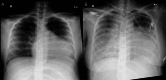

This study aimed to measure the concentrations of amiodarone (AM) and its active metabolite, mono-N-desethylamiodarone (DEA), in the breast milk of postpartum Japanese women treated with AM for ventricular tachycardia associated with peripartum cardiomyopathy and to conduct a follow-up study on the long-term growth and development of infants after resumption of breastfeeding. The patient was a 28-year-old Japanese woman with no underlying diseases who developed ventricular tachycardia and peripartum cardiomyopathy after giving birth. She was administered AM for three days via a combination of oral and intravenous administration. Breastfeeding began 35 days after the end of AM. Breast milk was collected 14 and 39 days after the end of AM, and its concentration in breast milk was measured using high-performance liquid chromatography. Furthermore, the growth and developmental test results of the twins were tracked for three years. Fourteen days after the end of AM administration, the AM concentration in breast milk was 111 ng/mL and the DEA concentration was 143 ng/mL. After 39 days, the AM concentration in breast milk was 11.8 ng/mL, and the DEA concentration in breast milk was 36.6 ng/mL. Studies have reported that pregnant women receiving AM are at risk of causing infant hypothyroidism and developmental delays due to the drug's high iodine content. Given the potential risks of invasive procedures and low milk intake, thyroid function testing was not conducted in the infant. Both twins were noted to be obese but had no clinical complications, and developmental evaluations showed no deficits. It was believed that resuming breastfeeding at that time was appropriate. Considering the risks associated with hypothyroidism, it is necessary to carefully determine the timing of breastfeeding initiation based on factors such as the mother's AM dosage, maternal blood concentration, and the infant's breast milk intake. However, it is considered acceptable for breastfeeding women who have received oral or intravenous AM for several days postpartum to breastfeed their infants.